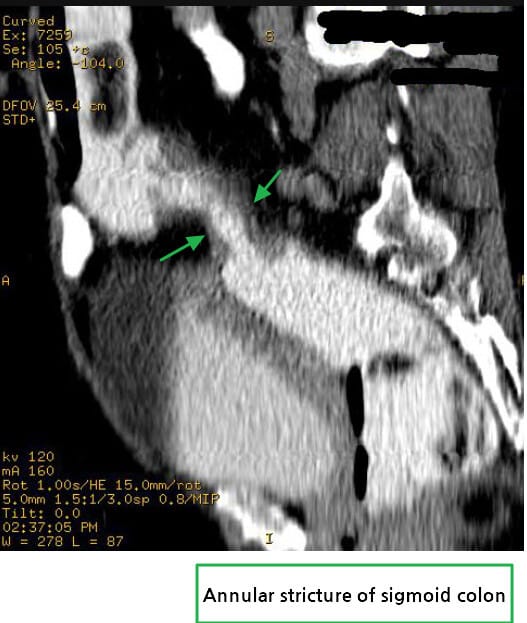

🔵 Annular constricting mass

암이 장을 원형으로 둘러싸며 협착을 유발하는 고전적 폐색 패턴입니다.

Abdrabou A, Carcinoma of sigmoid colon. Case study, Radiopaedia.org (Accessed on 15 Jul 2025) https://doi.org/10.53347/rID-23071